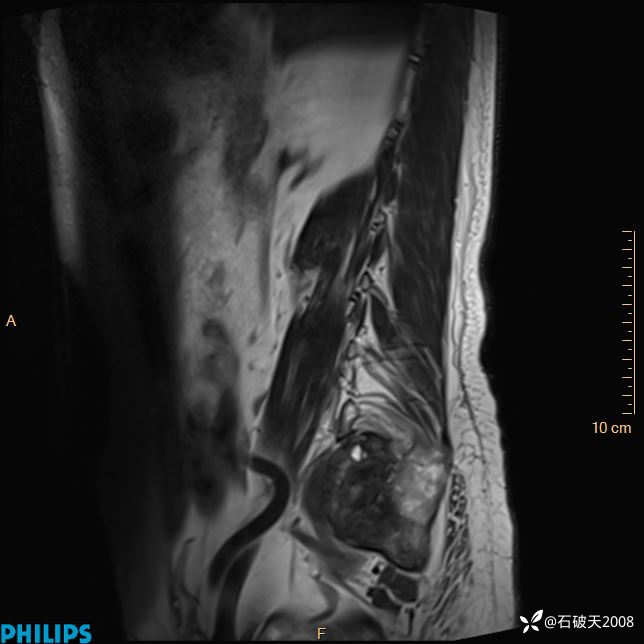

2023年3月份MRI影像

T2矢状位